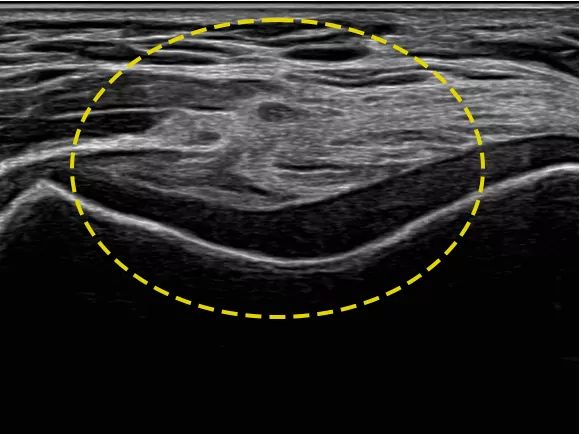

NerveTrack™ це функція, яка виявляє та надає інформацію про розташування ділянки нерва в режимі реального часу під час ультразвукового сканування.

NerveTrack™